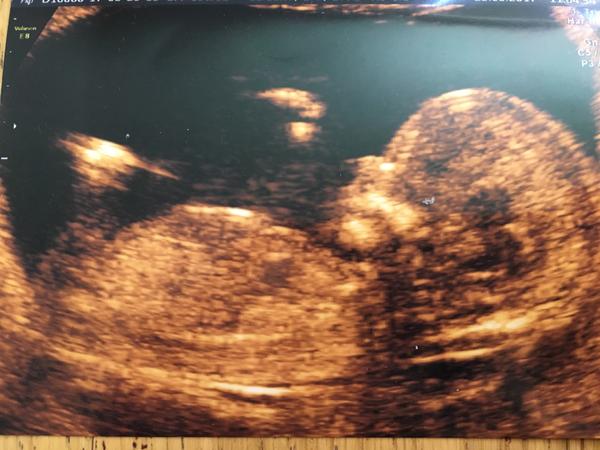

Je to holčička nebo chlapeček? Foto ultrazvuku

@kacenecka_24 Tady hrbolek vidět neni. :( Budes muset vydržet 🙂